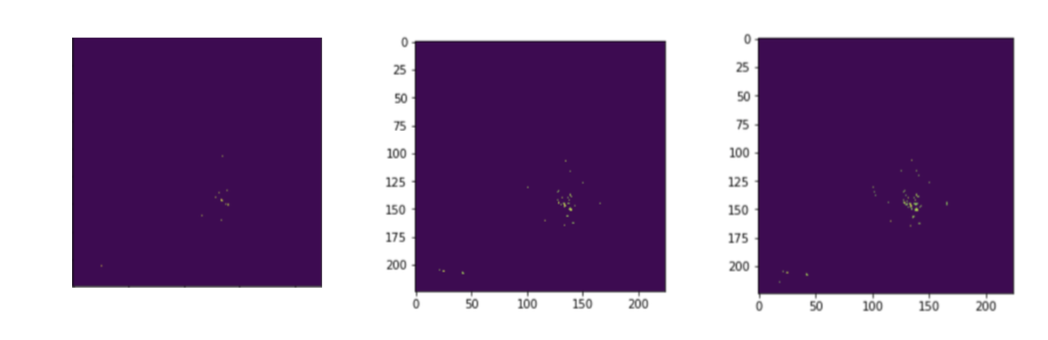

We address this issue by introducing a tuning parameter called sight sensitivity. Treating the image as a 2-D grid, this algorithm treats positive signals as points on a plane. These signals are obtained via the integrated gradients. These partial gradients of the image yield the influence of each pixel on the resulting classification decision. A large partial gradient value of a pixel is regarded as a positive signal. The sight sensitivity parameter is the threshold value which decides if a given gradient is large enough to be considered as a signal or not.

This parameter can be tuned to yield signal points on the 2-D grid. All other pixel gradients that fail to surpass this threshold are turned off (0 values). The remaining points are clustered in an unsupervised manner. Based on information loss criteria of distance, the points are clustered around their anomaly neighborhoods. The centroids of these clusters act as the center of the circles drawn around these bounding circles. The radius of the bound is equal to the farthest away point’s distance to its cluster’s center point.

Above methodology is depicted in Figure 2. The ground truth for the patient is: ”There are degenerative changes in the spine. Borderline enlarged heart.”. The detection in the low sight sensitivity setting (bottom right) lets too much signal pass through. The result of this is detailed bounds around the spinal area and with an emphasis on the heart, accompanied with noise on the bottom left portion of the image. The higher sight sensitivity (bottom left) produces an averaged out explanation without the structured noise by trading off some true positive signals.